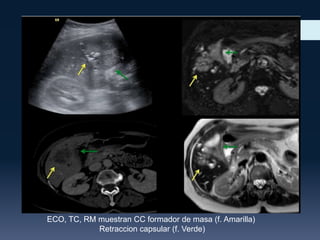

ECO, TC, RM muestran CC formador de masa (f. Amarilla)

Retraccion capsular (f. Verde)

ECO, TC, RMmuestran CC formador de masa (f. Amarilla) Retraccion capsular (f. Verde)